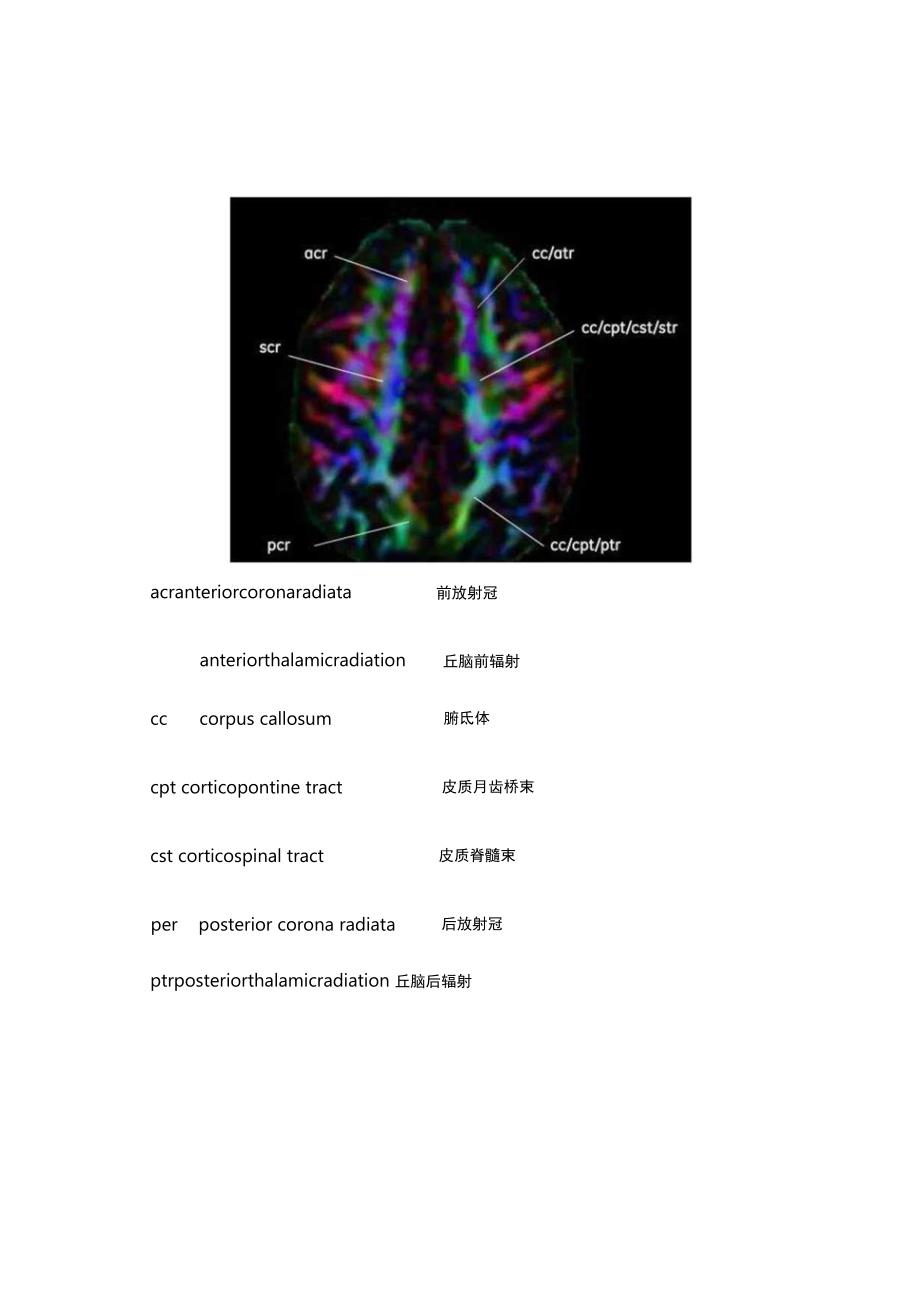

2、翻译)编辑此解剖图谱,希望对大家有用。本文是第一部分,为轴位高清DTI解剖图谱。后续会推出冠状和矢状位图谱,最终打算将其汇总为T分Pdf文档,方便查找。敬请期待!声明:本系列图谱图片来源于网络(几年前在网络上获取的,在我印象中来自GE官方教育网站,具体网址记不清了),同时也参考了一些外文资料,再此一并感谢。本文出于学习交流目的,图片版权归原作者所有。本文未经过严格校对,图文难免有错漏,同时英文简写全名也难免有误。还请大家指正。Axi-Iscrsuperiorcoronaradiata上放射冠CCcorpuscallosumfl三体CPtcorticopontinetract皮质脑桥束CStco

3、rticospinaltract皮质脊髓束strsuperiorthalamicradiation丘脑上辐射acranteriorcoronaradiata前放射冠丘脑前辐射anteriorthalamicradiationcccorpus callosum腑氐体cpt corticopontine tract皮质月齿桥束cst corticospinal tract皮质脊髓束perposterior corona radiata后放射冠ptrposteriorthalamicradiation丘脑后辐射strsuperiorthalamicradiation丘月圆上辐身寸acranterio

4、rcoronaradiata前放射冠atranteriorthalamicradiation丘月囱崩昌射cccorpus callosum崩脏体cpt corticopontine tract皮质脑桥束cst corticospinal tract皮质脊髓束posterior corona radiata后放射冠ptrposteriorthalamicradiation丘脑后辐射scrsuperior corona radiata上放射冠slfsuperiorlongitudinalfasciculus上tstrsuperiorthalamicradiation丘脑上辐射Ai-4atrante